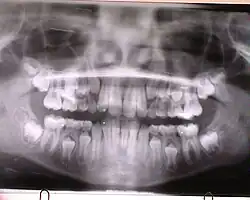

Dentition (von lat. dentire „zahnen“[1]) oder Zahnung ist der Durchbruch von Zähnen aus dem Kiefer in die Mundhöhle. Das Gebiss des Menschen und der meisten Säugetiere durchläuft zwei Dentitionen (Diphyodontie).

Der Durchbruch der bleibenden Zähne (Latein: dentes permanentes, (von latein: dens ‚Zahn‘, und permanere ‚verbleiben‘)[1]) erfolgt beim Menschen zwischen dem 6. und 14. Lebensjahr ebenfalls von vorne beginnend. Eine Ausnahme bilden die Weisheitszähne, die erst im Erwachsenenalter (bzw. im Alter von 16–30 Jahren) durchbrechen, sofern sie überhaupt angelegt sind.

Die ersten Molaren (sogenannte Sechsjahrmolaren) brechen meist vor allen anderen bleibenden Zähnen durch und weil sie in der Regel schon vor dem Verlust der Milchschneidezähne durchbrechen (daher auch Sechsjahrmolar genannt), werden sie von Laien oft als verspätete Milchzähne angesehen. Als solche werden sie bei der Zahnpflege oft vernachlässigt („die fallen ja doch aus“) und nehmen somit oft schon sehr früh Schaden. Da Milch-Eckzahn und Milchmolaren in der Summe breiter sind als der bleibende Eckzahn und die Prämolaren, ergibt sich in diesem Bereich während des Zahnwechsels ein Platzgewinn, der Leeway Space genannt wird.

Insgesamt sind wie im Milchgebiss auch im bleibenden Gebiss die unteren Zähne den oberen normalerweise „einen Schritt voraus“. Bemerkenswert ist die Tatsache, dass im Oberkiefer (nicht jedoch im Unterkiefer) die ersten Prämolaren (4-er) vor den Eckzähnen durchbrechen. Man nennt das den „Sprung um die Ecke“. Dies ermöglicht dem Caninus (3er) vom 1. Prämolar durch eine Einziehung („Kerbe“) an der Mesialfläche in die richtige Stellung geführt zu werden. Auch bei den bleibenden Zähnen sind hinsichtlich der Durchbruchszeiten Abweichungen möglich, insbesondere, wenn Milchzähne vorzeitig verloren gehen.